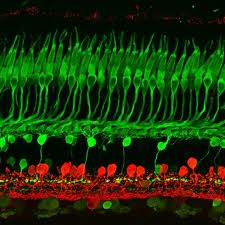

– Degeneración de las células ganglionares de la retina

lo que sugiere que ambas enfermedades pueden proceder de mecanismos de plegamiento similares. Una presentación de los caminos patogénicos comunes asociados con estos trastornos, incluyendo mecanismos de muerte celular, la producción de especies reactivas de oxígeno, la disfunción mitocondrial y anomalías vasculares, servirán como un punto de inicio para posteriores estudios.